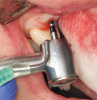

In preparation for the surgical procedure, modest bone grafting and soft-tissue augmentation was used to create more ideal oral parameters to receive the implants. Five implants (NobelActive®, Nobel Biocare, nobelbiocare.com) were placed in the maxillary anterior esthetic zone using haptic robotic guidance (Figure 3 and Figure 4). The procedure was entirely flapless, contributing to minimizing trauma for the patient. The surgeon, in full control of the robot, guided the arm to the planned implant positions while inspecting the soft-tissue type at the emergence, noting the bone quality, and monitoring adherence to the plan with the robotic system's intraoperative accuracy verification. The real-time audio and visual updates confirmed that the clinical parameters had been successfully achieved.

Fig 3. Implant placement using haptic robotic guidance. As osteotomies are prepared, the robotic arm locks the handpiece at the correct spatial position both in bodily direction and angulation, and as the clinician drills to proper depth, the arm prohibits further drilling apically.

Figure 3

Fig 4. Implant placement using haptic robotic guidance. As osteotomies are prepared, the robotic arm locks the handpiece at the correct spatial position both in bodily direction and angulation, and as the clinician drills to proper depth, the arm prohibits further drilling apically.

Figure 4